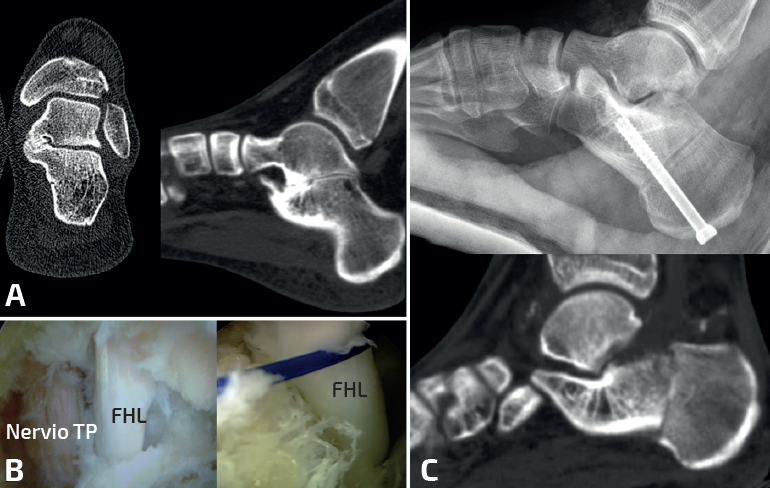

- Resección aislada de la coalición: indicada en casos de CA resecable y valgo del retropié menor de 16°. Mediante un abordaje medial sobre el sustentáculo tali se resecan aproximadamente 10 mm entre ambos huesos. Es importante respetar el sustentáculo tali, resecando más superficie del astrágalo que del calcáneo. A veces, es difícil identificar la coalición, sobre todo si es completamente ósea. La proyección radioscópica intraoperatoria de Harris puede ayudar a su localización, mientras que la TC intraoperatoria, las guías de corte con impresiones 3D o las técnicas de navegación están en desarrollo. La resección se considera completa cuando se consigue movilizar la articulación subastragalina y se visualiza la carilla articular posterior. Es importante interponer algún material como grasa para evitar reosificaciones. Las técnicas endoscópicas también están ganando popularidad, porque se visualiza y se reseca mejor la coalición que afecta a la carilla posterior, pero tienen una importante curva de aprendizaje y no se recomiendan en las coaliciones que afectan a la carilla media y anterior(13,14)(Figuras 5, 6 y 7).

- Resección de la coalición asociada a corrección del pie plano valgo: indicada en casos de CA resecable y valgo del retropié mayor de 16°. La resección de la coalición no restaura la morfología del pie, incluso puede empeorar el valgo del retropié. Se emplean técnicas como el alargamiento de la columna externa u osteotomía de deslizamiento medial del calcáneo, mejorando de forma significativa la función, la sintomatología y las imágenes radiográficas del pie. Si tras la corrección del valgo se objetiva supinación del antepié se asocia una osteotomía de flexión plantar de la primera cuña (Figura 8). La mayoría de los autores realizan ambos procesos simultáneamente. Otros autores recomiendan realizar ambos procedimientos en dos tiempos quirúrgicos separados en el tiempo, por las mismas razones que se han comentado anteriormente. Al igual que en las coaliciones CE, si existe una deformidad en valgo aumentada, preferimos realizar la cirugía simultáneamente.